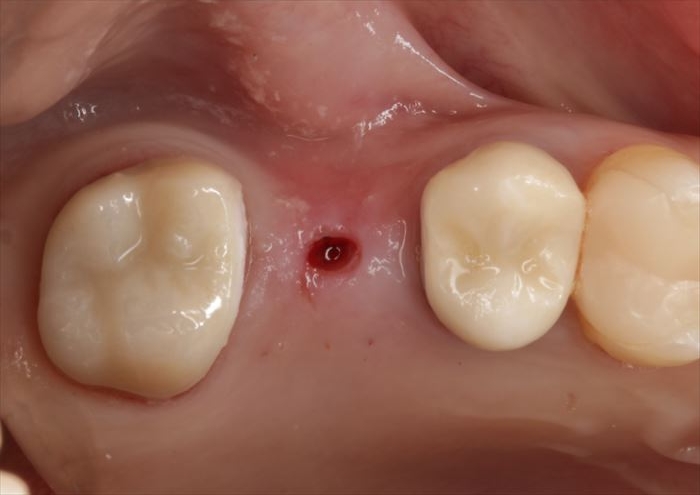

ドリルサイズを拡大してドリリングを終えました。

実際の骨の形を確認するために粘膜を剥離します。

頬側骨が少々足りない状況ですので、インプラント埋入後に骨増生処置(GBR)を行います。

スイス ストローマン社製のインプラントを用います。

BLT Roxolid φ4.1㎜ 長さ8㎜

インプラントの埋入を終えました。